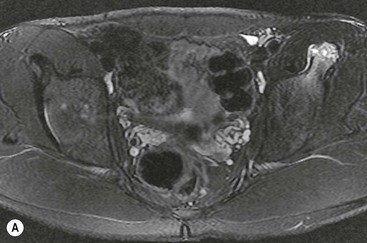

Pincer-type impingement, more common in middle-aged women, results from overcoverage of the femoral head by the acetabulum. This can be due to a deep acetabulum, bone hypertrophy at the acetabular rim or abnormal acetabular retroversion, the latter leading to an effective overcoverage of the femoral head anteriorly. On hip flexion the abnormal morphology results in impingement between the acetabular rim and the femoral neck, leading to labral and cartilage damage. The centre-edge angle is a method to identify acetabular overcoverage on an AP radiograph of the pelvis (Fig. 46-38). A centre-edge angle greater than 40° may be considered abnormal.23 Coxa profunda and protusio acetabuli are two types of deformity that predispose to pincer-type impingement. Coxa profunda is identified on an AP radiograph when the floor of the acetabular fossa overlaps the ilioischial line. Protrusio acetabuli, more severe, is present when the femoral head itself overlaps the ilioischial line (Fig. 46-38).